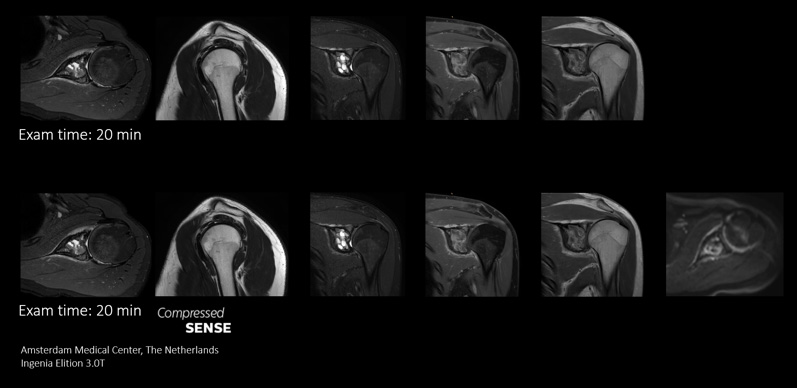

Replace sequences

Trade one sequence for a more powerful sequence

In some cases, like brain and spine examinations, it can be useful to use the power of Compressed SENSE to trade 2D MRI scan sequences for faster 3D sequences. This can allow clinicians to achieve high spatial resolution in tiny nerves and vessels.

Replace Sequences scan

With Compressed SENSE you can replace your single orientation 2D FLAIR scan with a multi-orientation 3D volumetric FLAIR scan in only 3 and a half minutes scan time.

I do a lot of brain imaging, and we used to do the FLAIR sequence using a 5 mm thick slice. Now with Compressed SENSE we are able to take a 3D volumetric scan for about 6 minutes down to maybe 3 and a half minutes.”

Dr. Mark Oswood, MD, PhD, Neuroradiologist, Hennepin Healthcare, Minneapolis, USA

Add Sequences Scan

This case demonstrates the ability to add additional sequences within the same time slot to enhance your diagnostic confidence. Besides traditional TSE sequences, you can now add a functional DWI sequence within the same timeslot, providing additional information for you to base your diagnosis on.